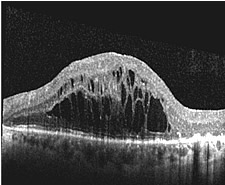

| OCT-Bild einer normalen Makula (Stelle des schärfsten Sehens der Netzhaut) mit typischer zentraler Einsenkung (Fovea) | OCT-Bild der Makula eines Patienten mit großen flüssigkeitsgefüllten Zysten im Bereich der Stelle des schärfsten Sehens der Netzhaut | |||||||||

Alle schwerwiegenden Erkrankungen des Augenhintergrundes gehen mit einer Strukturveränderung der mehrschichtigen Netzhaut oder des Sehnervens einher. Hierbei kann es in Abhängigkeit der Erkrankung beispielsweise zur Entstehung von Löchern in der Stelle des schärften Sehens (Makulaforamen), Zysten in der Netzhaut (diabetische Retinopathie), Wassereinlagerungen unter der Netzhaut (Makuladegeneration), Anschwellungen des Sehnerven (Durchblutungsstörungen) oder Aushöhlungen des Sehnerven (Glaukom) kommen. Eine den Patienten nicht belastende Untersuchung, mit der die Veränderungen von Netzhaut und Sehnerv dreidimensional sichtbar gemacht werden können, ist die optrische Computer-Tomographie, bei der mit einem niedrig-energetischen Laserstrahl der Augenhintergrund zeilenweise abgetastet und aus den reflektierten Lichtanteilen ein hochauflösendes Schichtbild gewonnen wird.